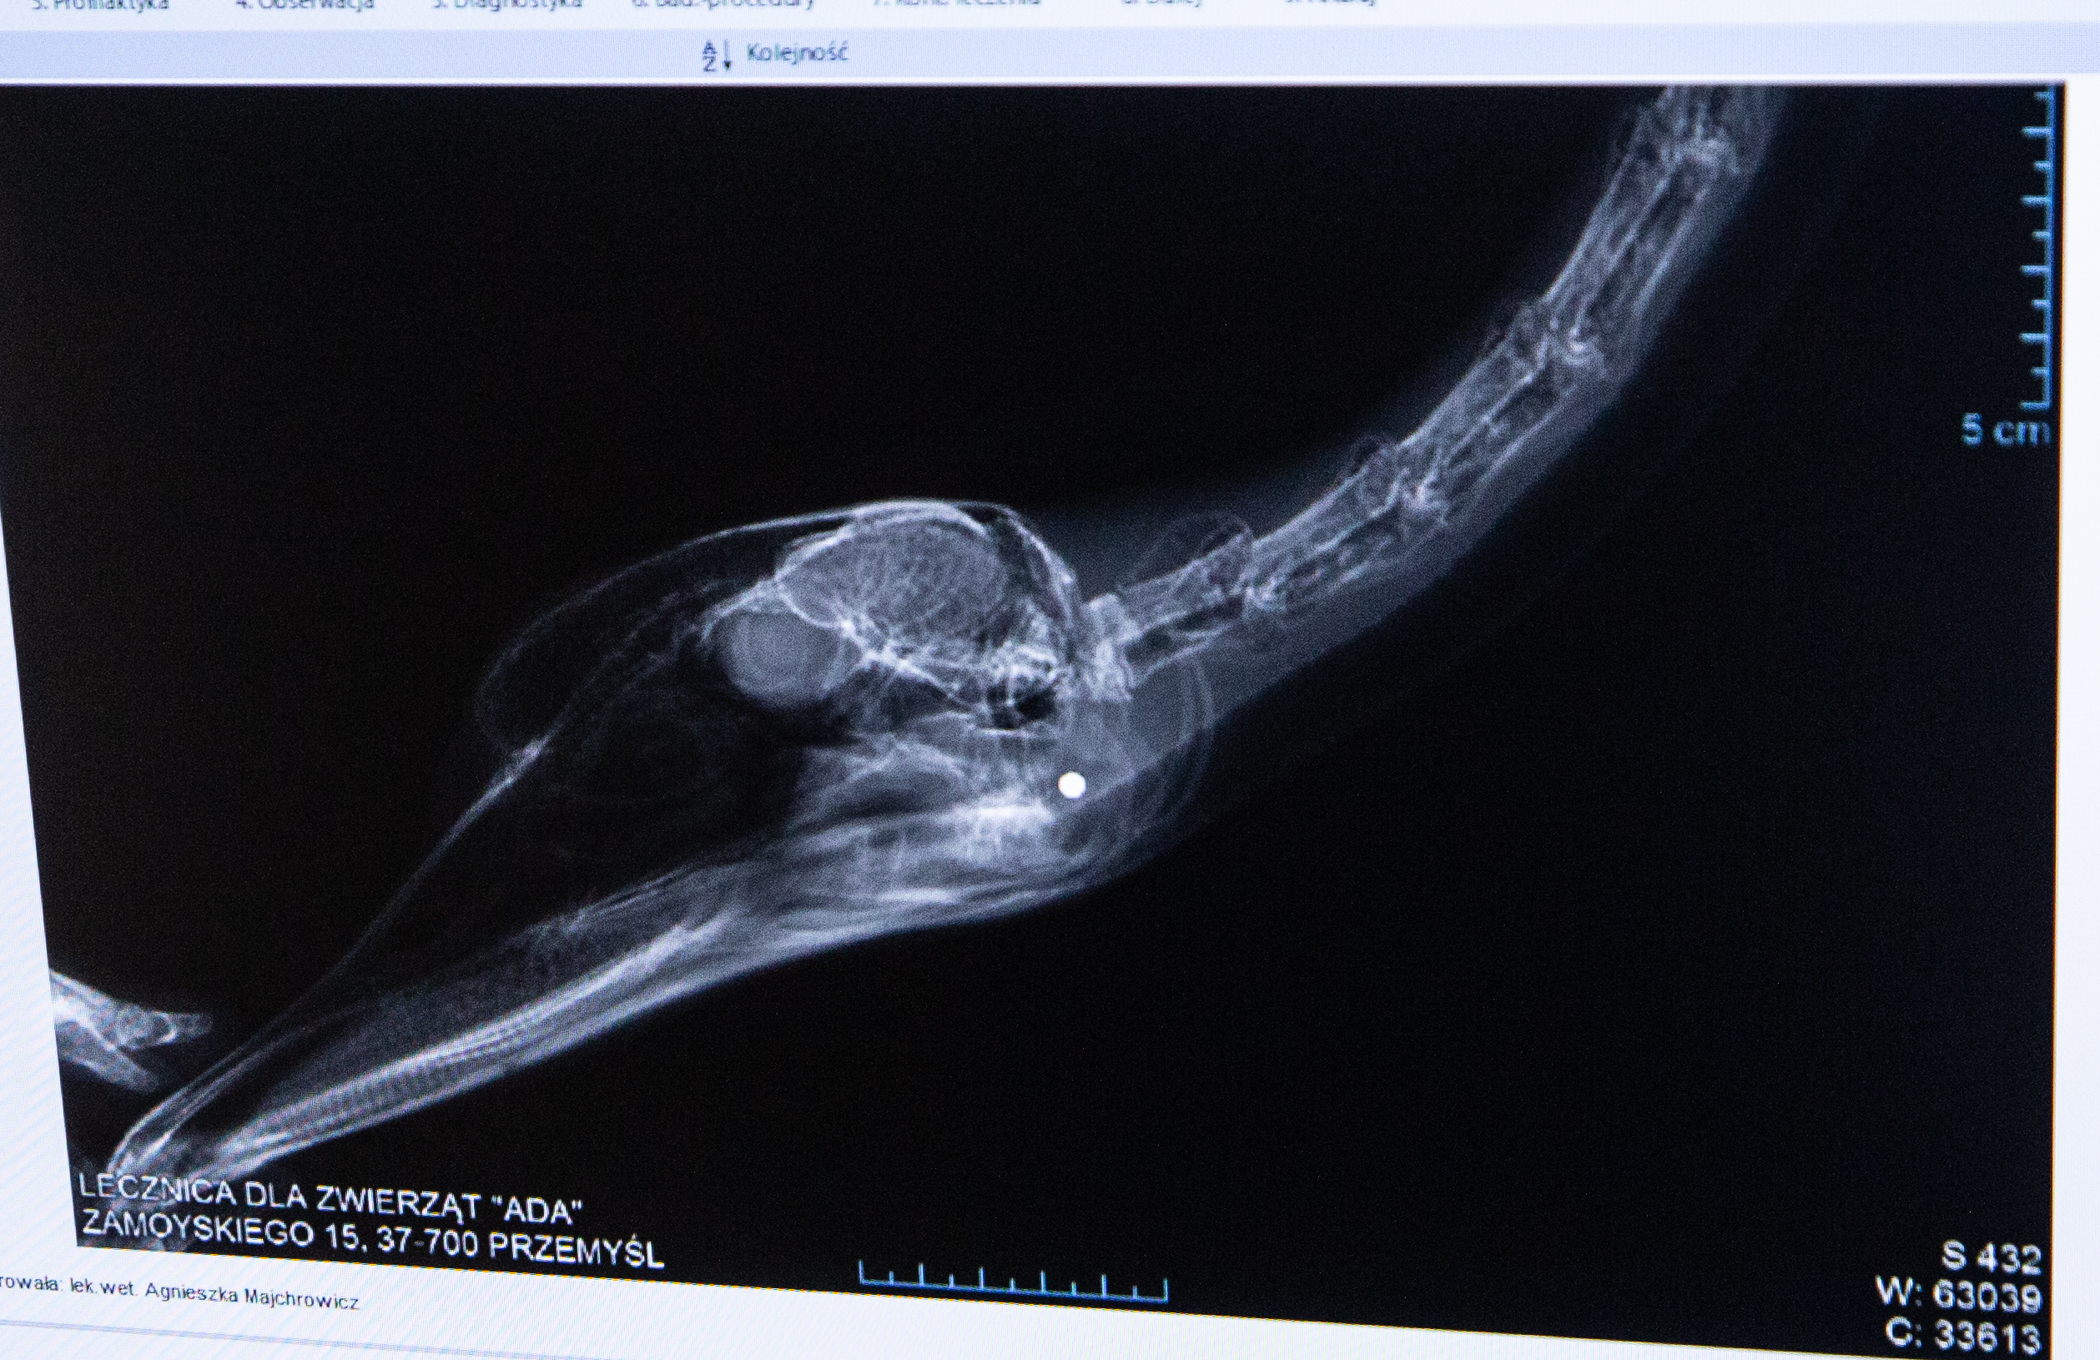

Oli Łabędź Ptak królewski brutalnie postrzelony przed zwyrodnialca trafił po ratunek do Fundacji ADA w stanie ciężkim. Dwa śruty ciało obce zakrwawione wycieńczone bólem i urazami Zwierzę z trudem oddychało kryjąc się polach.